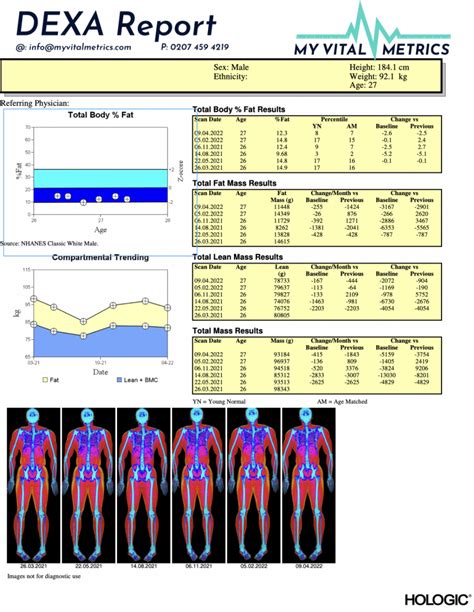

Dexa Scan Report Template